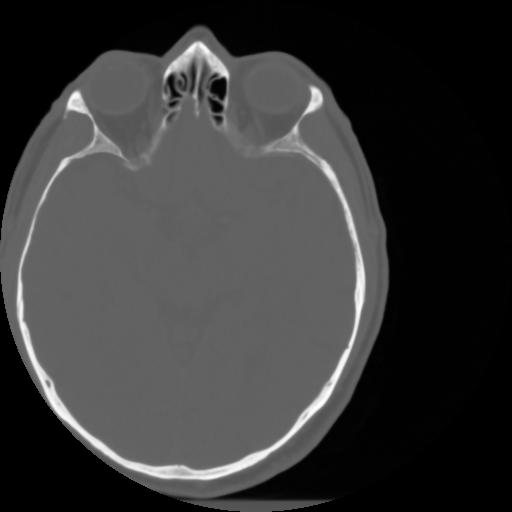

3 CEREBRO,,Axial,3.0,CEREBRO,,